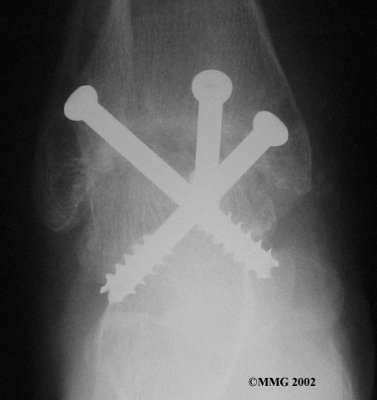

It is important when the surfaces are removed that the angles of the cut surfaces are correct. When the tibia is brought against the talus, the foot should be at a right angle to the lower leg. Once the cuts are made the bones must be held in place while they fuse. This can be done using large metal screws and metal plates if necessary. The screws are usually under the skin and are not removed unless they begin to rub and cause pain.

Inserting the screws

After ankle fusion, the physical therapists at FYZICAL Cypress North can help you learn to walk smoothly and without a limp. Although time needed for recovery varies among patients, an ankle brace will typically replace your cast after eight to 12 weeks. Your surgeon will take X-rays frequently to see if the bones are fusing together. You will probably need to use crutches during the time you wear the cast. As the fusion grows stronger, you will begin to put more weight on your foot when walking.